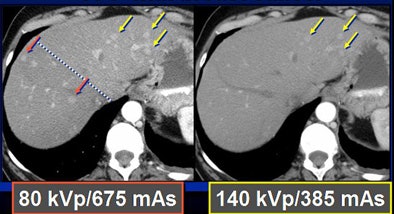

Because low kVp is closer to the K-edge of iodine, the attenuation of iodine structures increases as kVp decreases. Thus, a CT image of an iodine structure imaged at 140 kVp is about 200; dropping the kVp to 80 nearly doubles the attenuation, even though tube energy is reduced, Nelson explained.

In a phantom model tested by the Duke team, iodine structures were seen more clearly when attenuation was reduced. Similar results were found in patients with hepatic lesions; some subtly hyperenhancing liver lesions could be seen only at lower kVp levels.

To test the hypothesis quantitatively, Duke researchers performed a study of 48 patients with 68 hyperenhancing live lesions, scanned using a dual-energy volume technique (GE Healthcare, Chalfont St. Giles, U.K.) during the arterial phase, Nelson said. One rotation was scanned at 80 kVp and 540 mAs; a second was acquired at 140 kVp and 308 mAs. The results showed significant differences in lesion conspicuity with the use of low-kVp imaging.